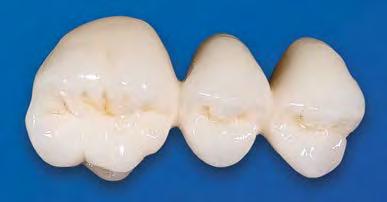

El innovador Disilicato de Litio (LS2) del sistema de cerámica vítrea IPS e.max CAD no solo ofece una altísima estética sino que también es de 2,5 a 3 veces más resistente 360 MPa que el resto de cerámicas de vidrio. Por ello, este material cubre todos los requerimientos estéticos y también representa una alternativa eficiente a las restauraciones unitarias de Zr02 (Zirconio).

El innovador Disilicato de Litio (LS2) del sistema de cerámica vítrea IPS e.max CAD no solo ofrece una altísima estética sino que también es de 2,5 a 3 veces más resistente 360 MPa que el resto de cerámicas de vidrio. Por ello, este material cubre todos los requerimientos estéticos y también representa una alternativa eficiente a las restauraciones unitarias de ZrO2. (Zirconio)

IPS e.max está avalado por la experiencia clínica que ha demostrado durante años, tanto en estética como en resistencia. La amplitud de elección del material, según el caso, en conjunción con la técnica empleada en nuestro laboratorio dotarán a los trabajos de la mayor estética para sus pacientes.